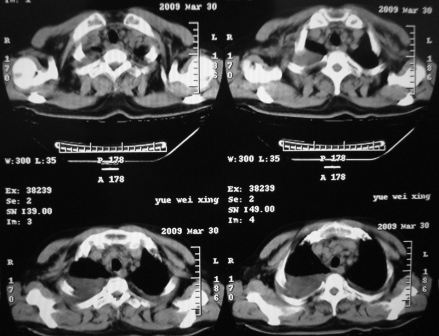

病史呢?先考虑----右中央型肺癌继发下叶不张,双肺及纵隔淋巴转移,双侧胸腔积液,心包积液。

不排除---心脏病变所致

先考虑----右中央型肺癌继发下叶不张,双肺及纵隔淋巴转移,双侧胸腔积液,心包积液。